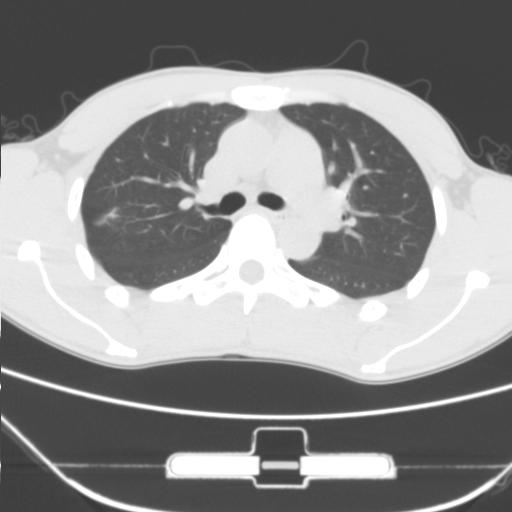

右肺上叶后段近胸膜下结节样异常密度灶,似见分页及毛刺,考虑右肺上叶周围型肺ca,建议穿刺病理检查

缺乏病史,症状体征,但这个孤立结节具备了几乎所有的恶性征象:分叶,毛刺,空泡征,胸膜凹陷征,血管集束。

考虑右肺上叶后段周围型肺癌。